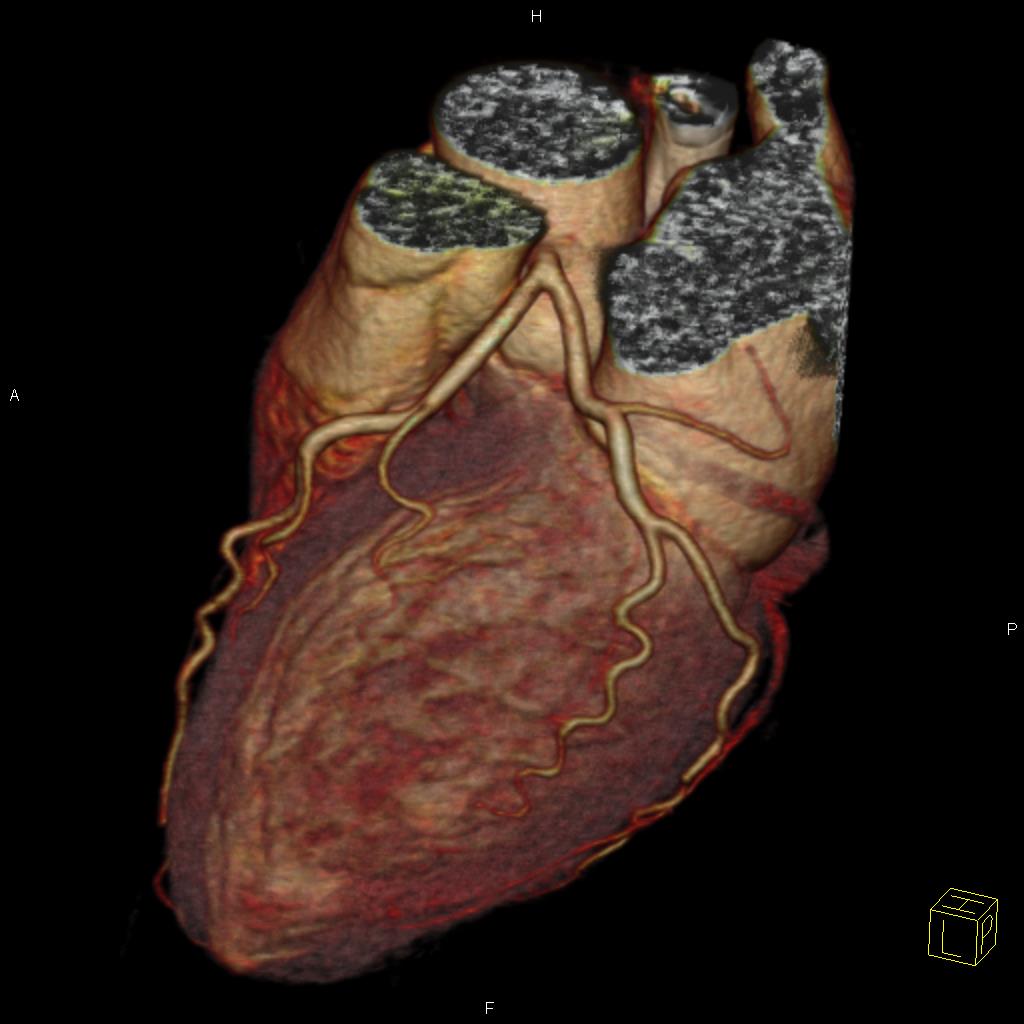

Sie hat sich als eine bedeutende Methode zur nichtinvasiven, das heisst unblutigen Darstellung der Herzkranzgefäße etabliert. Mit Hilfe der CT können bei angemessen ausgewählten und vorbereiteten Patienten mit grosser Zuverlässigkeit Aussagen über das Vorhandensein möglicher Engstellen oder Verschlüsse der Herzkranzgefässe (Abbildung 1), das Ausmass der Herzkranzgefässverkalkungen und die Anatomie des Herzens getroffen werden, und das ohne Herzkatheteruntersuchung. Sind die Herzkranzgefässe bereits erkrankt, so kann unter bestimmten Bedingungen auch eine Darstellung von Bypassgefässen (Abbildung 2) oder Stents erfolgen. Eine blutige Untersuchung mittels Herzkatheter kann somit in vielen Fällen vermieden werden (Abbildung 3). Sollten in der CT relevante Engstellen in einem oder mehreren Koronargefäßen auffallen, muss jedoch meist eine Herzkatheteruntersuchung zur weiterführenden Diagnostik und ggf. Therapie erfolgen.

Abbildung 3: Darstellung unauffälliger Herzkranzgefäße mittels kardialer CT. Eine Herzkatheteruntersuchung ist hier nicht notwendig.